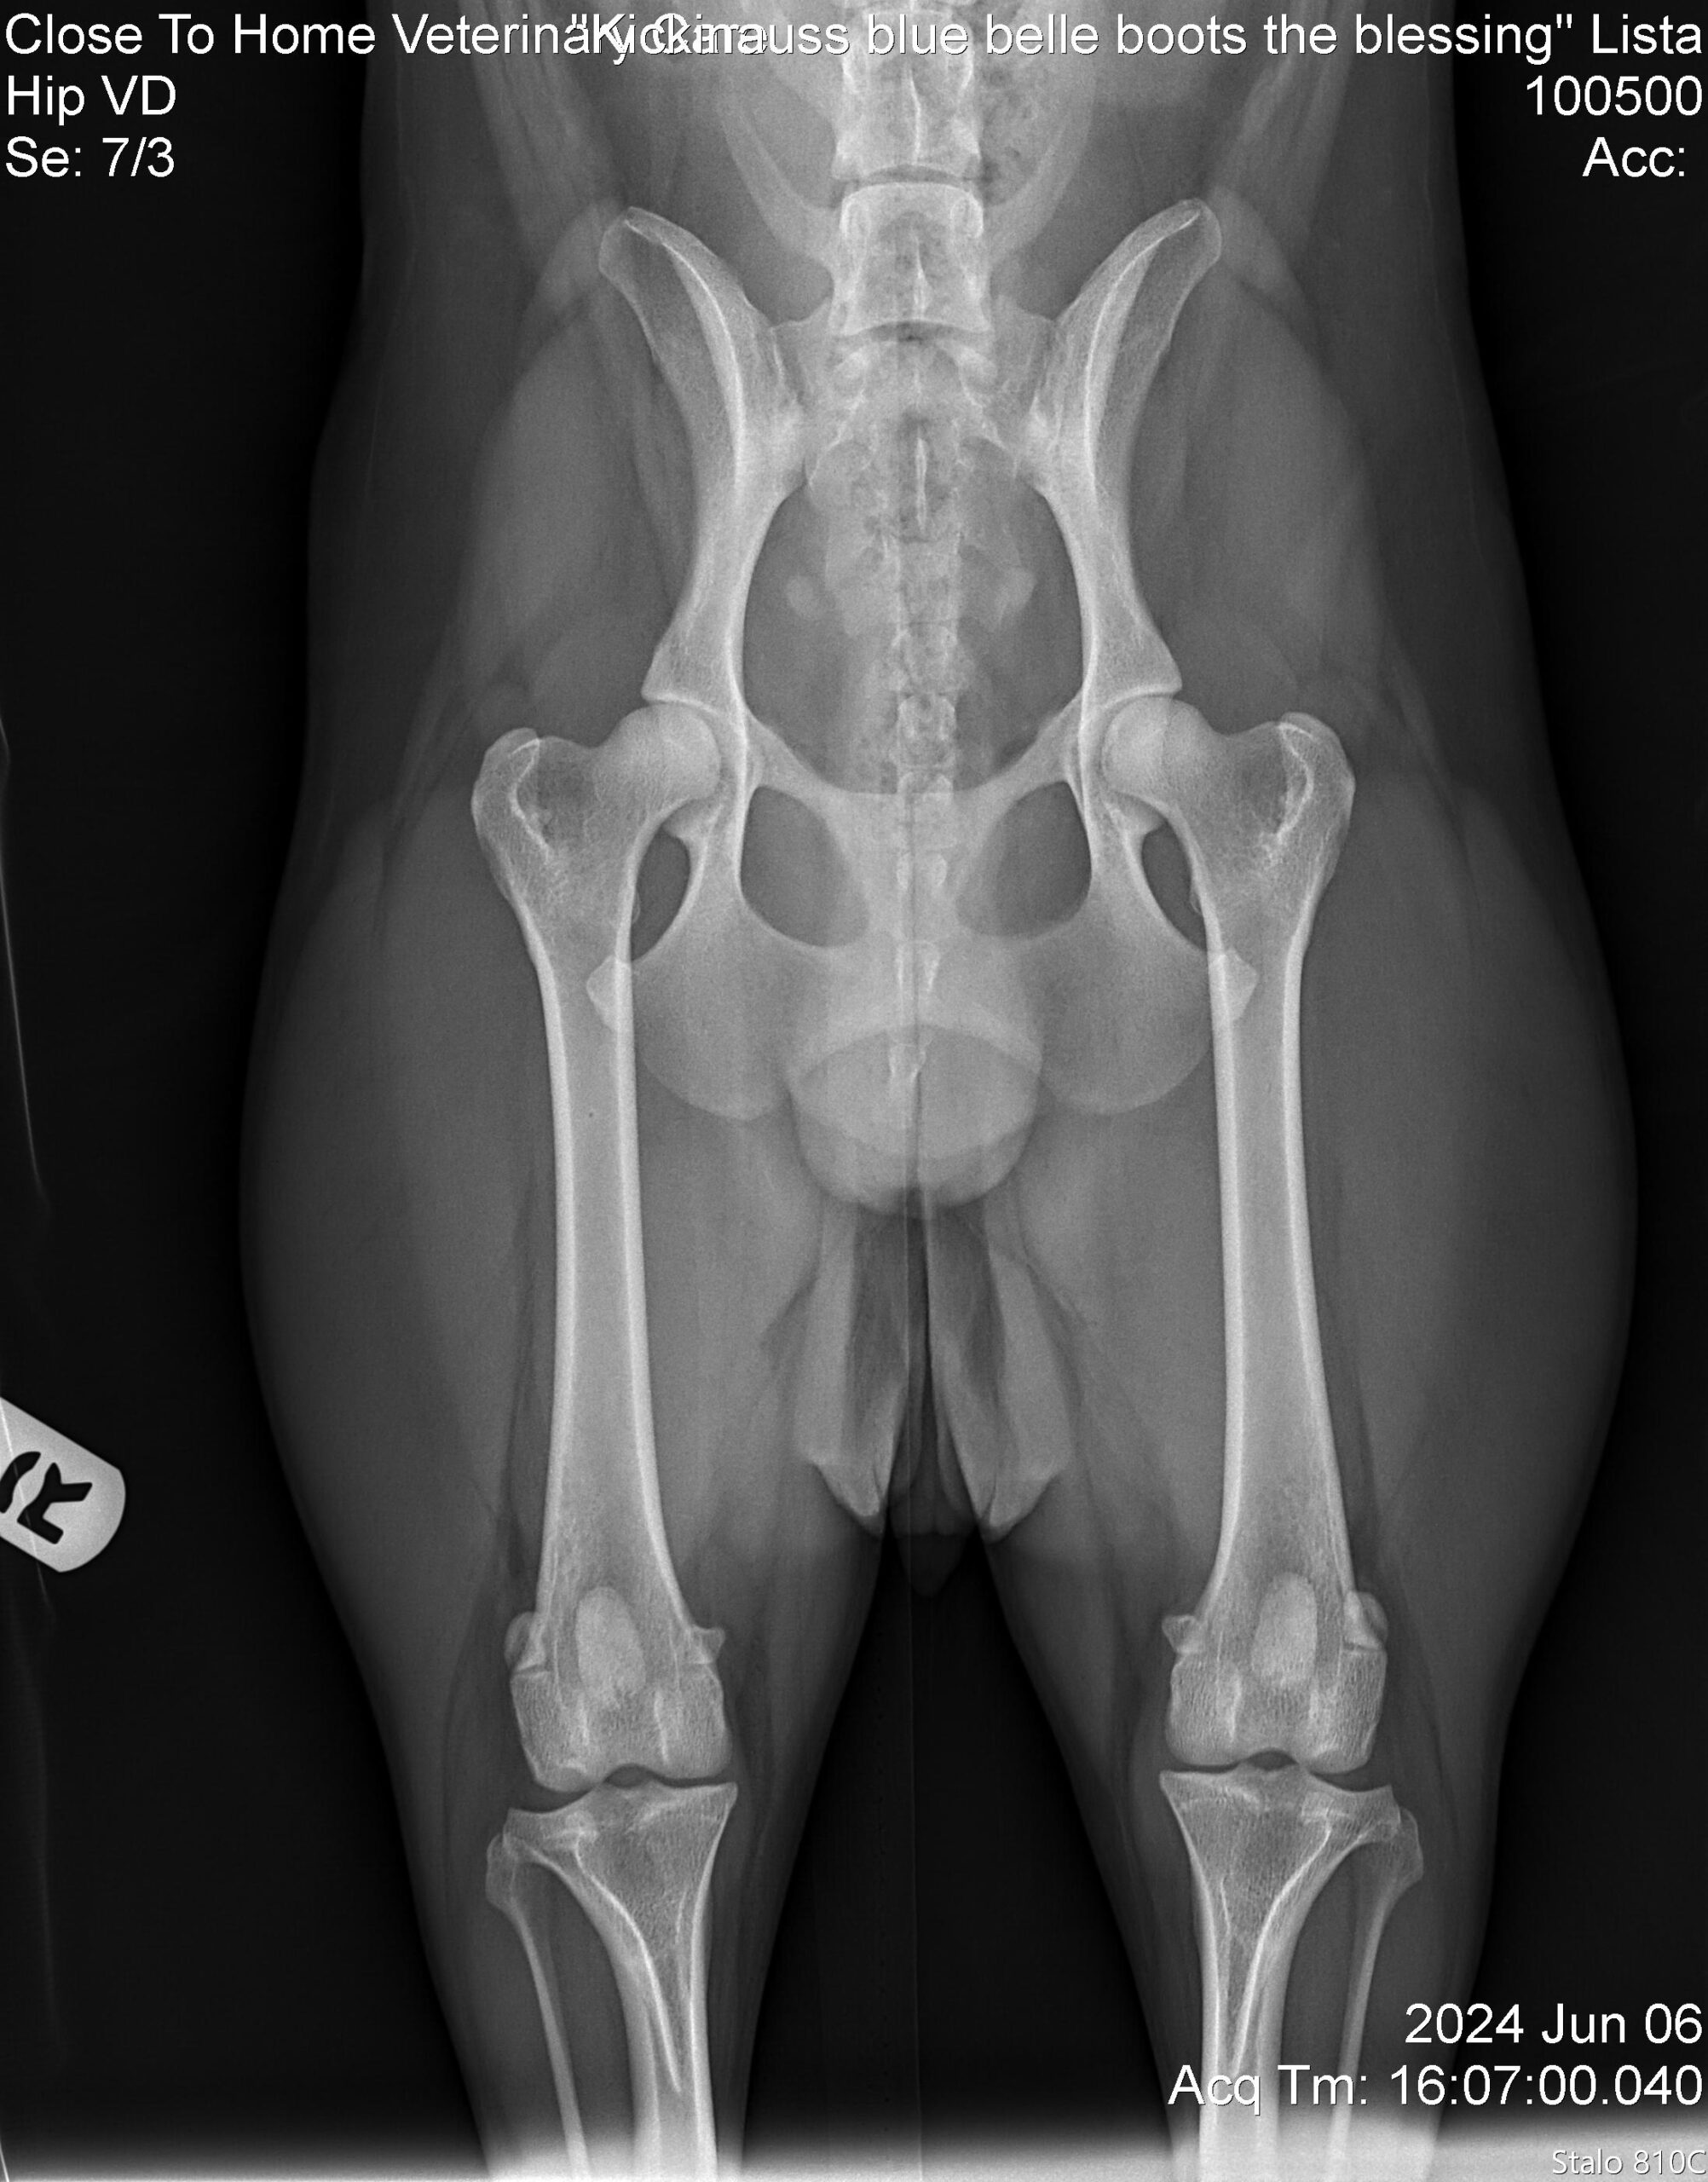

Have you ever heard about Dog Hip Dysplasia?

Dog hip dysplasia is a genetic condition that affects the hip joint, where the ball and socket of the hip do not fit together properly. In dogs with hip dysplasia, the joint is loose and unstable, causing the ball to move abnormally within the socket. Over time, this abnormal movement leads to joint damage, inflammation, pain, and arthritis.

Here are some reasons why it is so important to screen your dog for Hip Dysplasia (typically done at 24 months):